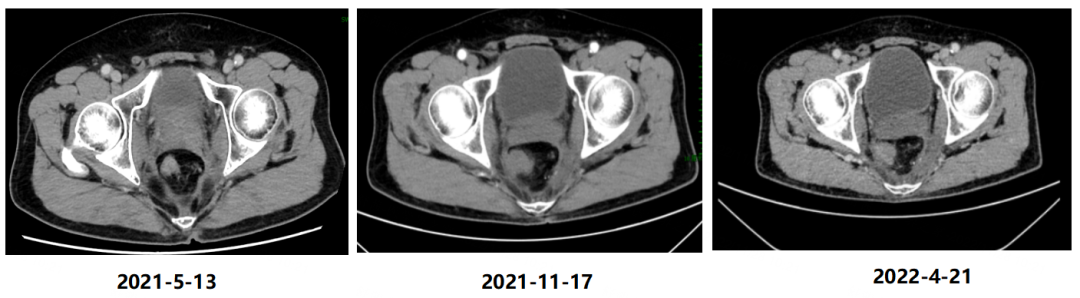

2021年5月13日开始每3个月复查1次,疗效评估均为持续PR。

图7 盆腔CT